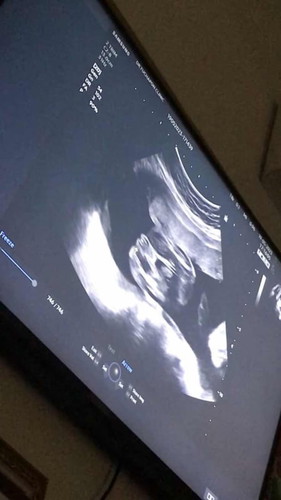

ในรูปตรงที่ลูกศรชี้ แม่ๆว่าผู้หญิง100%ไหมคะ #ทีมกันยา66 #ท้องแรกคะ #คุณแม่ๆช่วยแนะนำหน่อยค่ะ

100% ค่ะ กลีบ เม็ดชัดมาก ๆ แม่